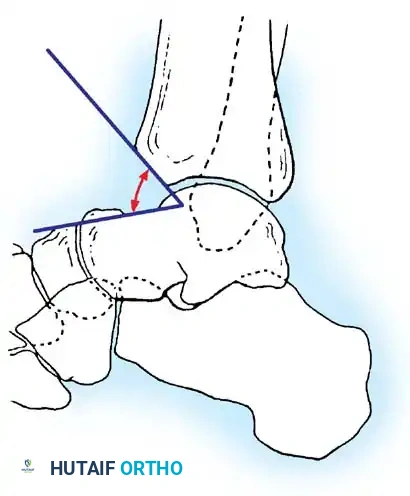

Transmalleolar Portals

As originally described by Guhl, transmalleolar portals are advanced techniques reserved for addressing osteochondral defects of the posterior-central portion of the talus that cannot be reached via standard portals.

Medial transmalleolar portal trajectory.

Lateral transmalleolar portal trajectory.

- Technique: These portals are established 2 to 3 cm proximal to the tip of the medial or lateral malleolus. Under direct arthroscopic visualization from an anterior portal, a 0.062-inch Kirschner wire is inserted using an anterior cruciate ligament (ACL) tibial guide for pinpoint accuracy. The wire is advanced across the malleolus to drill the chondral lesion. The ankle can be dynamically plantarflexed or dorsiflexed to allow drilling of the lesion in various locations.